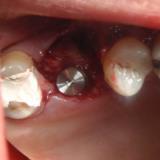

Immediate Implant Placement

A molar either maxillary or mandible always represents a little difficult and tricky scenario for implant placement immediately after extarction. There is always some sacrifice for the location, angle etc. however you save some time and patients go through a procedure once and it is a reliable method of replacing a tooth, when feasible. Dental implant is always a compromised replacement and a tooth restored with immediate placement is not any different.